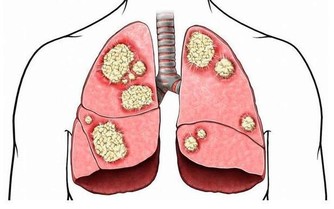

紋身過程不衛生,不規範,會增大感染乙肝、艾滋病、細菌性紅眼病和沙眼、梅毒、結核病等的風險。